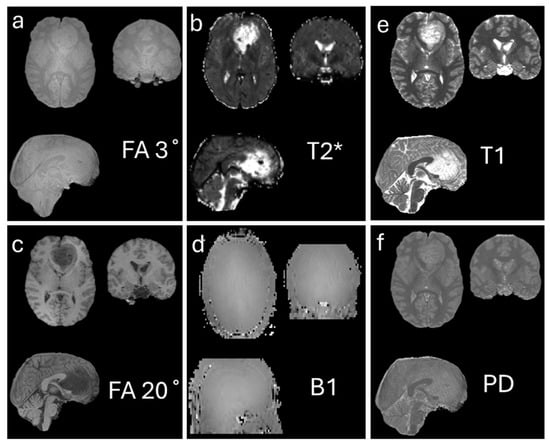

- Carter, F.; Anwander, A.; Johnson, M.; Goucha, T.; Adamson, H.; Friederici, A.D.; Lutti, A.; Gauthier, C.J.; Weiskopf, N.; Bazin, P.L.; et al. Assessing quantitative MRI techniques using multimodal comparisons. PLoS ONE 2025, 20, e0327828. [Google Scholar] [CrossRef]